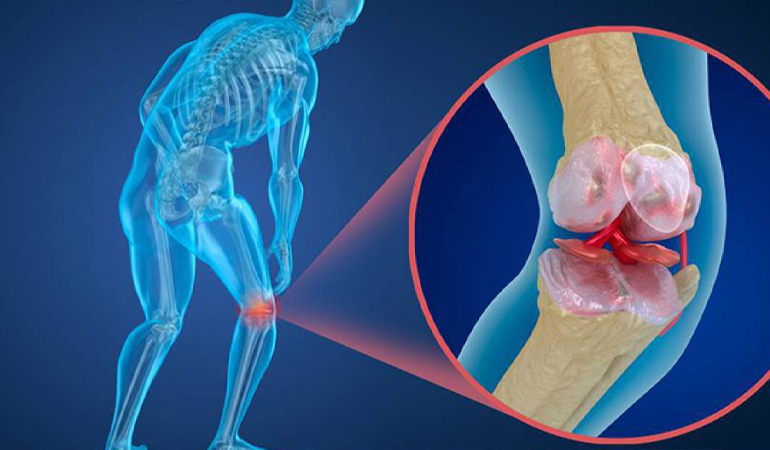

Hastalığın ilerlemesiyle boyda kısalma ve sırtta kamburlaşma görülüyor. Kırıklar, özellikle sırt omurlarında çökme tarzında, el bileği ve kalça kırıkları olarak ortaya çıkıyor. Omurga kırıkları, gövdede öne eğilme ve kamburluğa neden olabilir. Kırıklar ani ve şiddetli ağrıya yol açıyor.

Prof. Dr. Akman, menopoz sonrası kadınlar ve 65 yaş üstü erkeklerin düzenli kemik mineral yoğunluğu ölçümü yaptırmasını önerdi. Bu ölçüm, ağrısız ve hızlı bir şekilde kemik kaybını tespit ediyor. Tedavi yöntemleri arasında Çöken omur içine çimento enjeksiyonu (hızlı rahatlama) ve Korse, ağrı kesiciler, cerrahi yöntemler ve ilaç tedavileri bulunuyor.